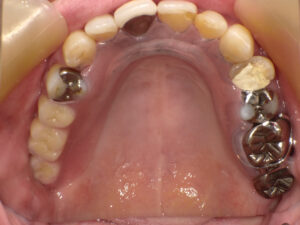

歯を抜いた後は、ミラクルデンチャーを入れられました。

術後

何度か入れ歯を入れた後は調整をしましたが、今では何でも噛めて、

歯に力を入れられようになったと、とても喜んでみえました。